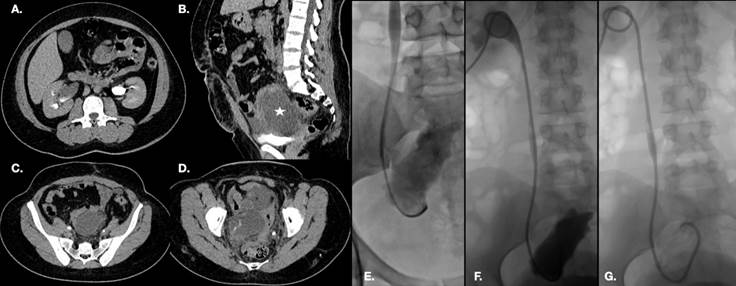

Se realiza tomografía computada con contraste intravenoso que muestra retardo en eliminación del riñón derecho (A), así como presencia de una colección de contenido líquido en hueco pélvico (estrella en B). Se identifica el trayecto ureteral bilateral hasta el tercio distal (C), con pérdida abrupta de la porción terminal del uréter derecho y fuga del medio de contraste a la colección descrita, lo cual es compatible con un urinoma (D). Se realiza tracto de nefrostomía y se avanza catéter multipropósito que evidencía la comunicación del uretero derecho con el urinoma (E). Se coloca estent nefroureteral (F) con el extremo distal en el urinoma, la J proximal en la pelvis renal y con extremo proximal del catéter conectado a una bolsa recolectora. En la imagen de control (G) se observa resolución del urinoma.

Figura 11 Paciente de 52 años con antecedente de histerectomía, que se presenta a urgencias con dolor abdominal